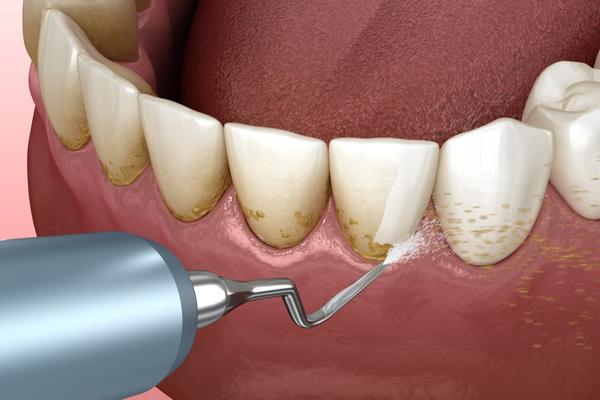

Scaling is a type of cleaning that uses a speci...